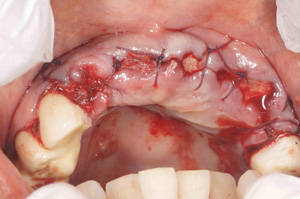

H.K‚³‚ñ 61Π —«@‰ïŽÐˆõ @Žèp“ú

‚Q‚O‚O‚X”N ‚RŒŽ‚Q‚V“úi‹àj  ãŠ{ƒm[ƒxƒ‹ƒKƒCƒhŽg—p@Ö¬“à’ÁÖ@•¹—p

@@@  @ ãŠ{ ‚R–{@”‚P‚U•” with Socket Lift and GBR   ’x‰„‰×d@

Nobel Speedy Groovy Rp ‚WD‚T mm

@@    @  @@@@@@@@”‚Q‚UE”‚Q‚V•”   ’x‰„‰×d

@   Rpl Tapered Wp ‚P‚O mm (‚Q–{)